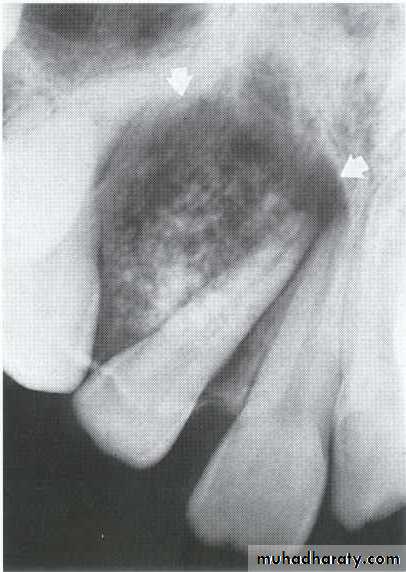

Central giant cell granuloma*A relatively uncommon, non- neoplastic mass in the jaws producing an expansile radiolucent soap bubble appearance.

*Age; <20 years. Female > Male.

*Teeth are vital, with some root resorption & migration of teeth. *History of trauma.

Multilocular appearance, expansion (arrowed) and considerable displacement of the adjacent teeth.

Buccal and lingual expansion (arrowed) and the undulating cortical border.